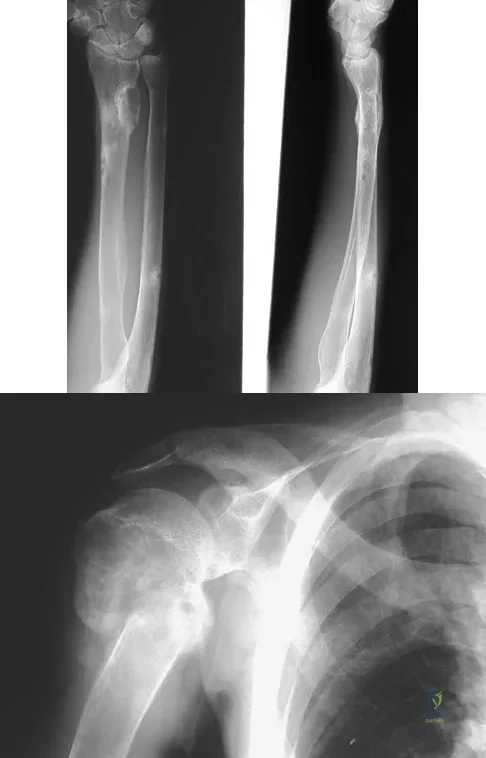

A 29-year-old woman reports shoulder pain after sustaining a minor fall 6 weeks ago. She has a history of celiac sprue. Radiographs of the forearm and shoulder are shown in Figures 53a and 53b. Which of the following serum abnormalities would be expected?